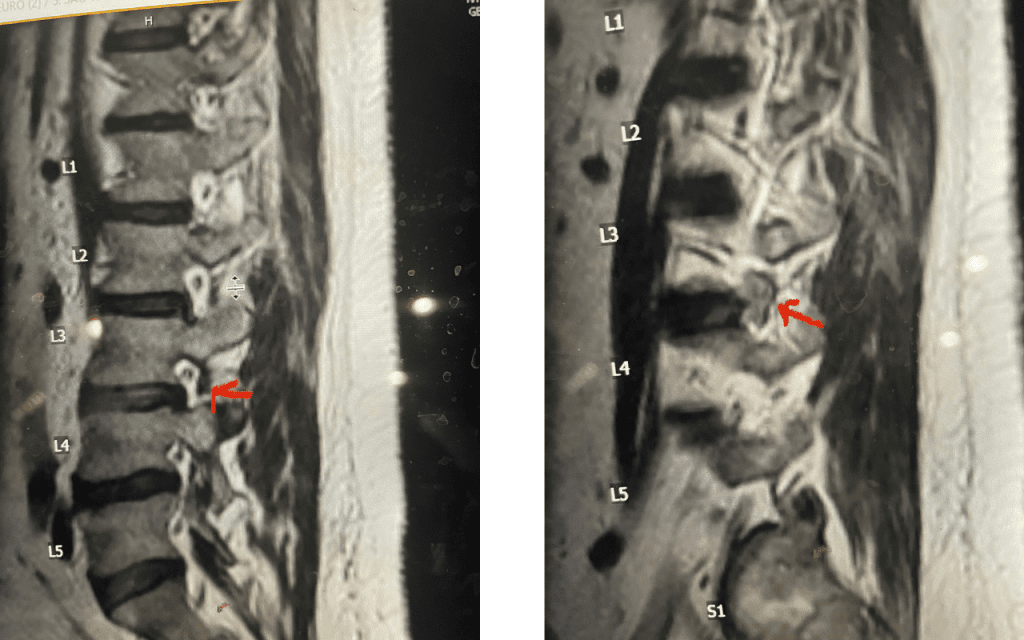

Fig 4: Axial and Sagittal T2-weighted lumbar MRI demonstrating a left lateral foraminal disc herniation (red arrow) causing compression of the exiting L1 nerve root against the undersurface of the pedicle of L1.